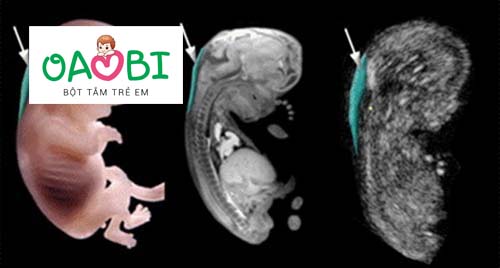

Chiều dài xương mũi thai nhi chuẩn theo tuần mẹ nên biết?

theo dõi chiều dài xương mũi giúp bác sĩ chẩn đoán thai nhi có bị dị tật nguy hiểm hay không để từ đó đưa ra cách xử lý kịp thời.